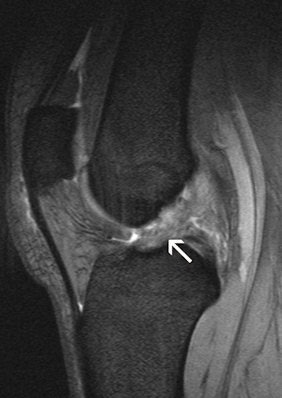

Anterior cruciate ligament tear. MRI reveals a swollen cruciate ligament; the knee joint can no longer be stabilized.

Anterior cruciate ligament tear. MRI reveals a swollen cruciate ligament; the knee joint can no longer be stabilized.The next job for the radiologist and later also for the orthopedic specialist is to correlate the images with the patient's symptoms and find a suitable therapy. The reason, as Stäbler makes absolutely clear, is that "the patient is always right; the question is to get the symptoms under control. To do this, the doctor must also feel the knee and interpret any swelling or redness correctly. This, together with the images, will set him on the right track."